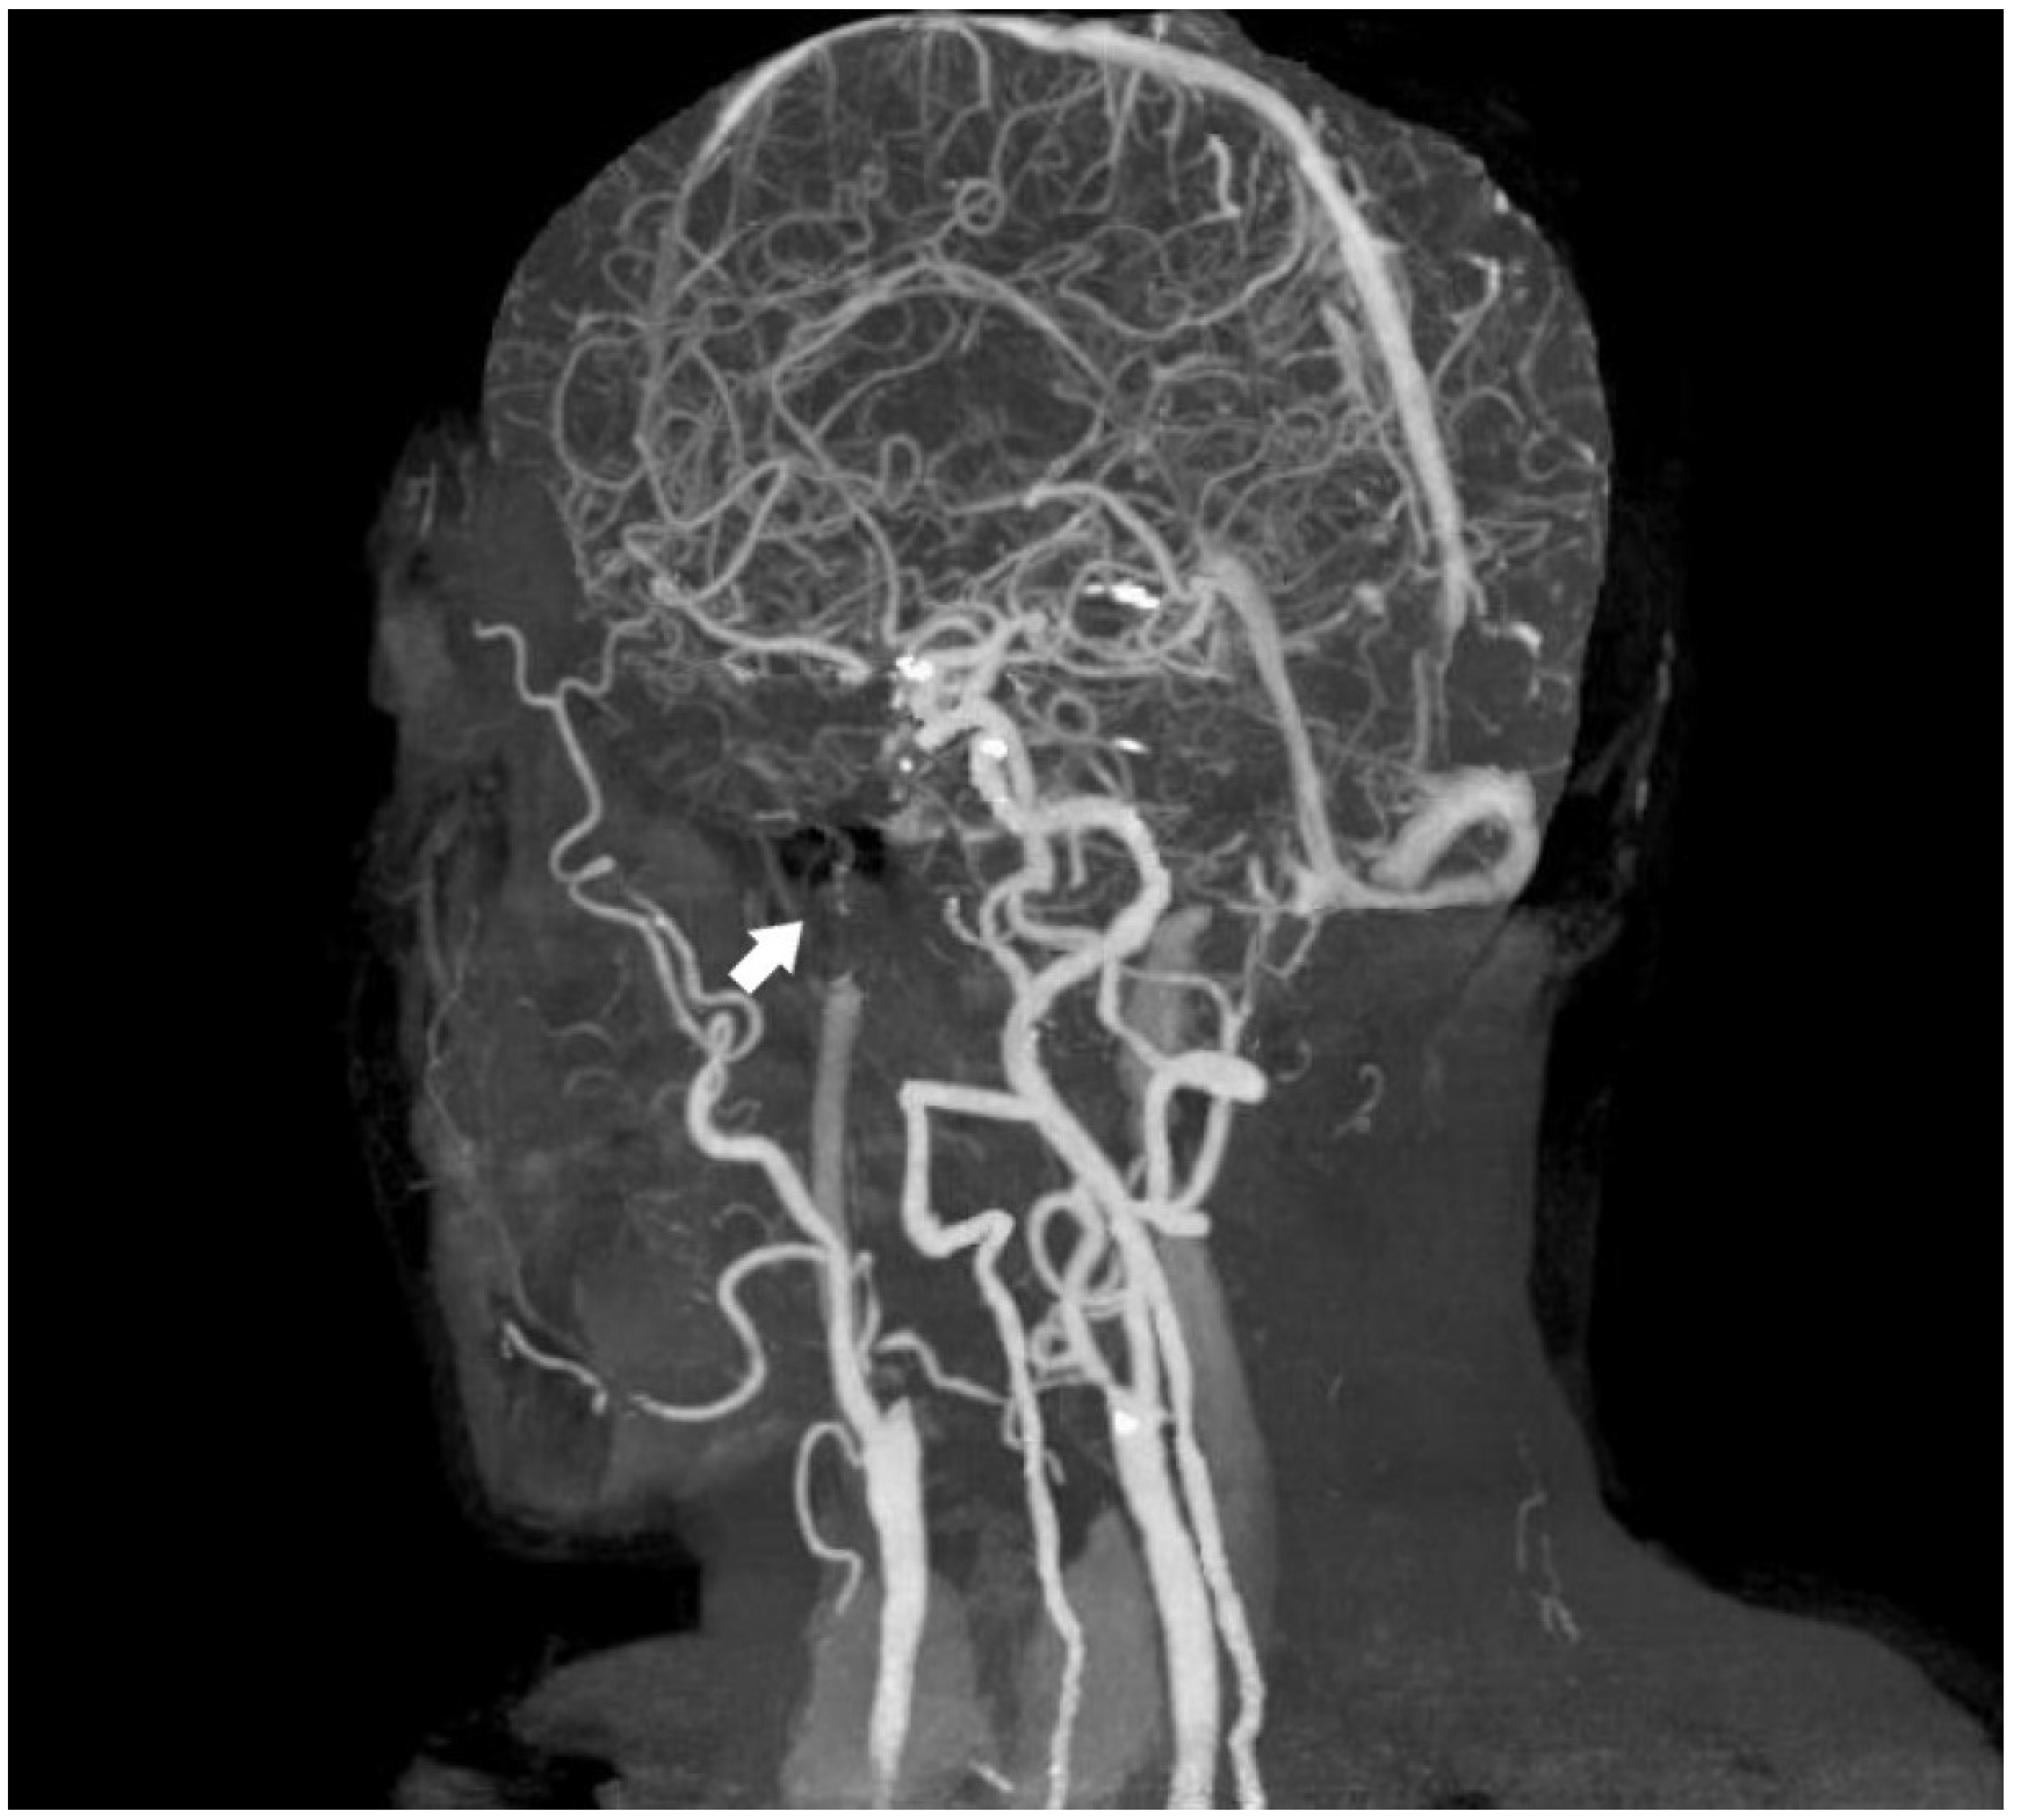

A 70-year-old male patient has presented with ongoing complaints of headache [VAS scale 6], pulsatile tinnitus [TFI level 3], and occasional dizziness. Neurological examination has revealed intact cranial nerves, bilaterally normal cerebellar function, normal deep tendon reflexes, a negative Romberg test, and preserved muscle strength. No abnormalities have been detected in other systemic examinations. Laboratory investigations showed no remarkable abnormalities. However, prior laboratory records indicated dyslipidemia for which the patient was under treatment, and he also had a known history of primary hypertension. Cranial MRI and MR angiography have demonstrated an absence of flow in the left internal carotid artery (Figure 1 and Figure 2).

Figure 1.

Absence of the left internal carotid artery on cranial MRI angiography [Time of Flight images (TOF), White arrow: no contrast filling in the carotid siphon].